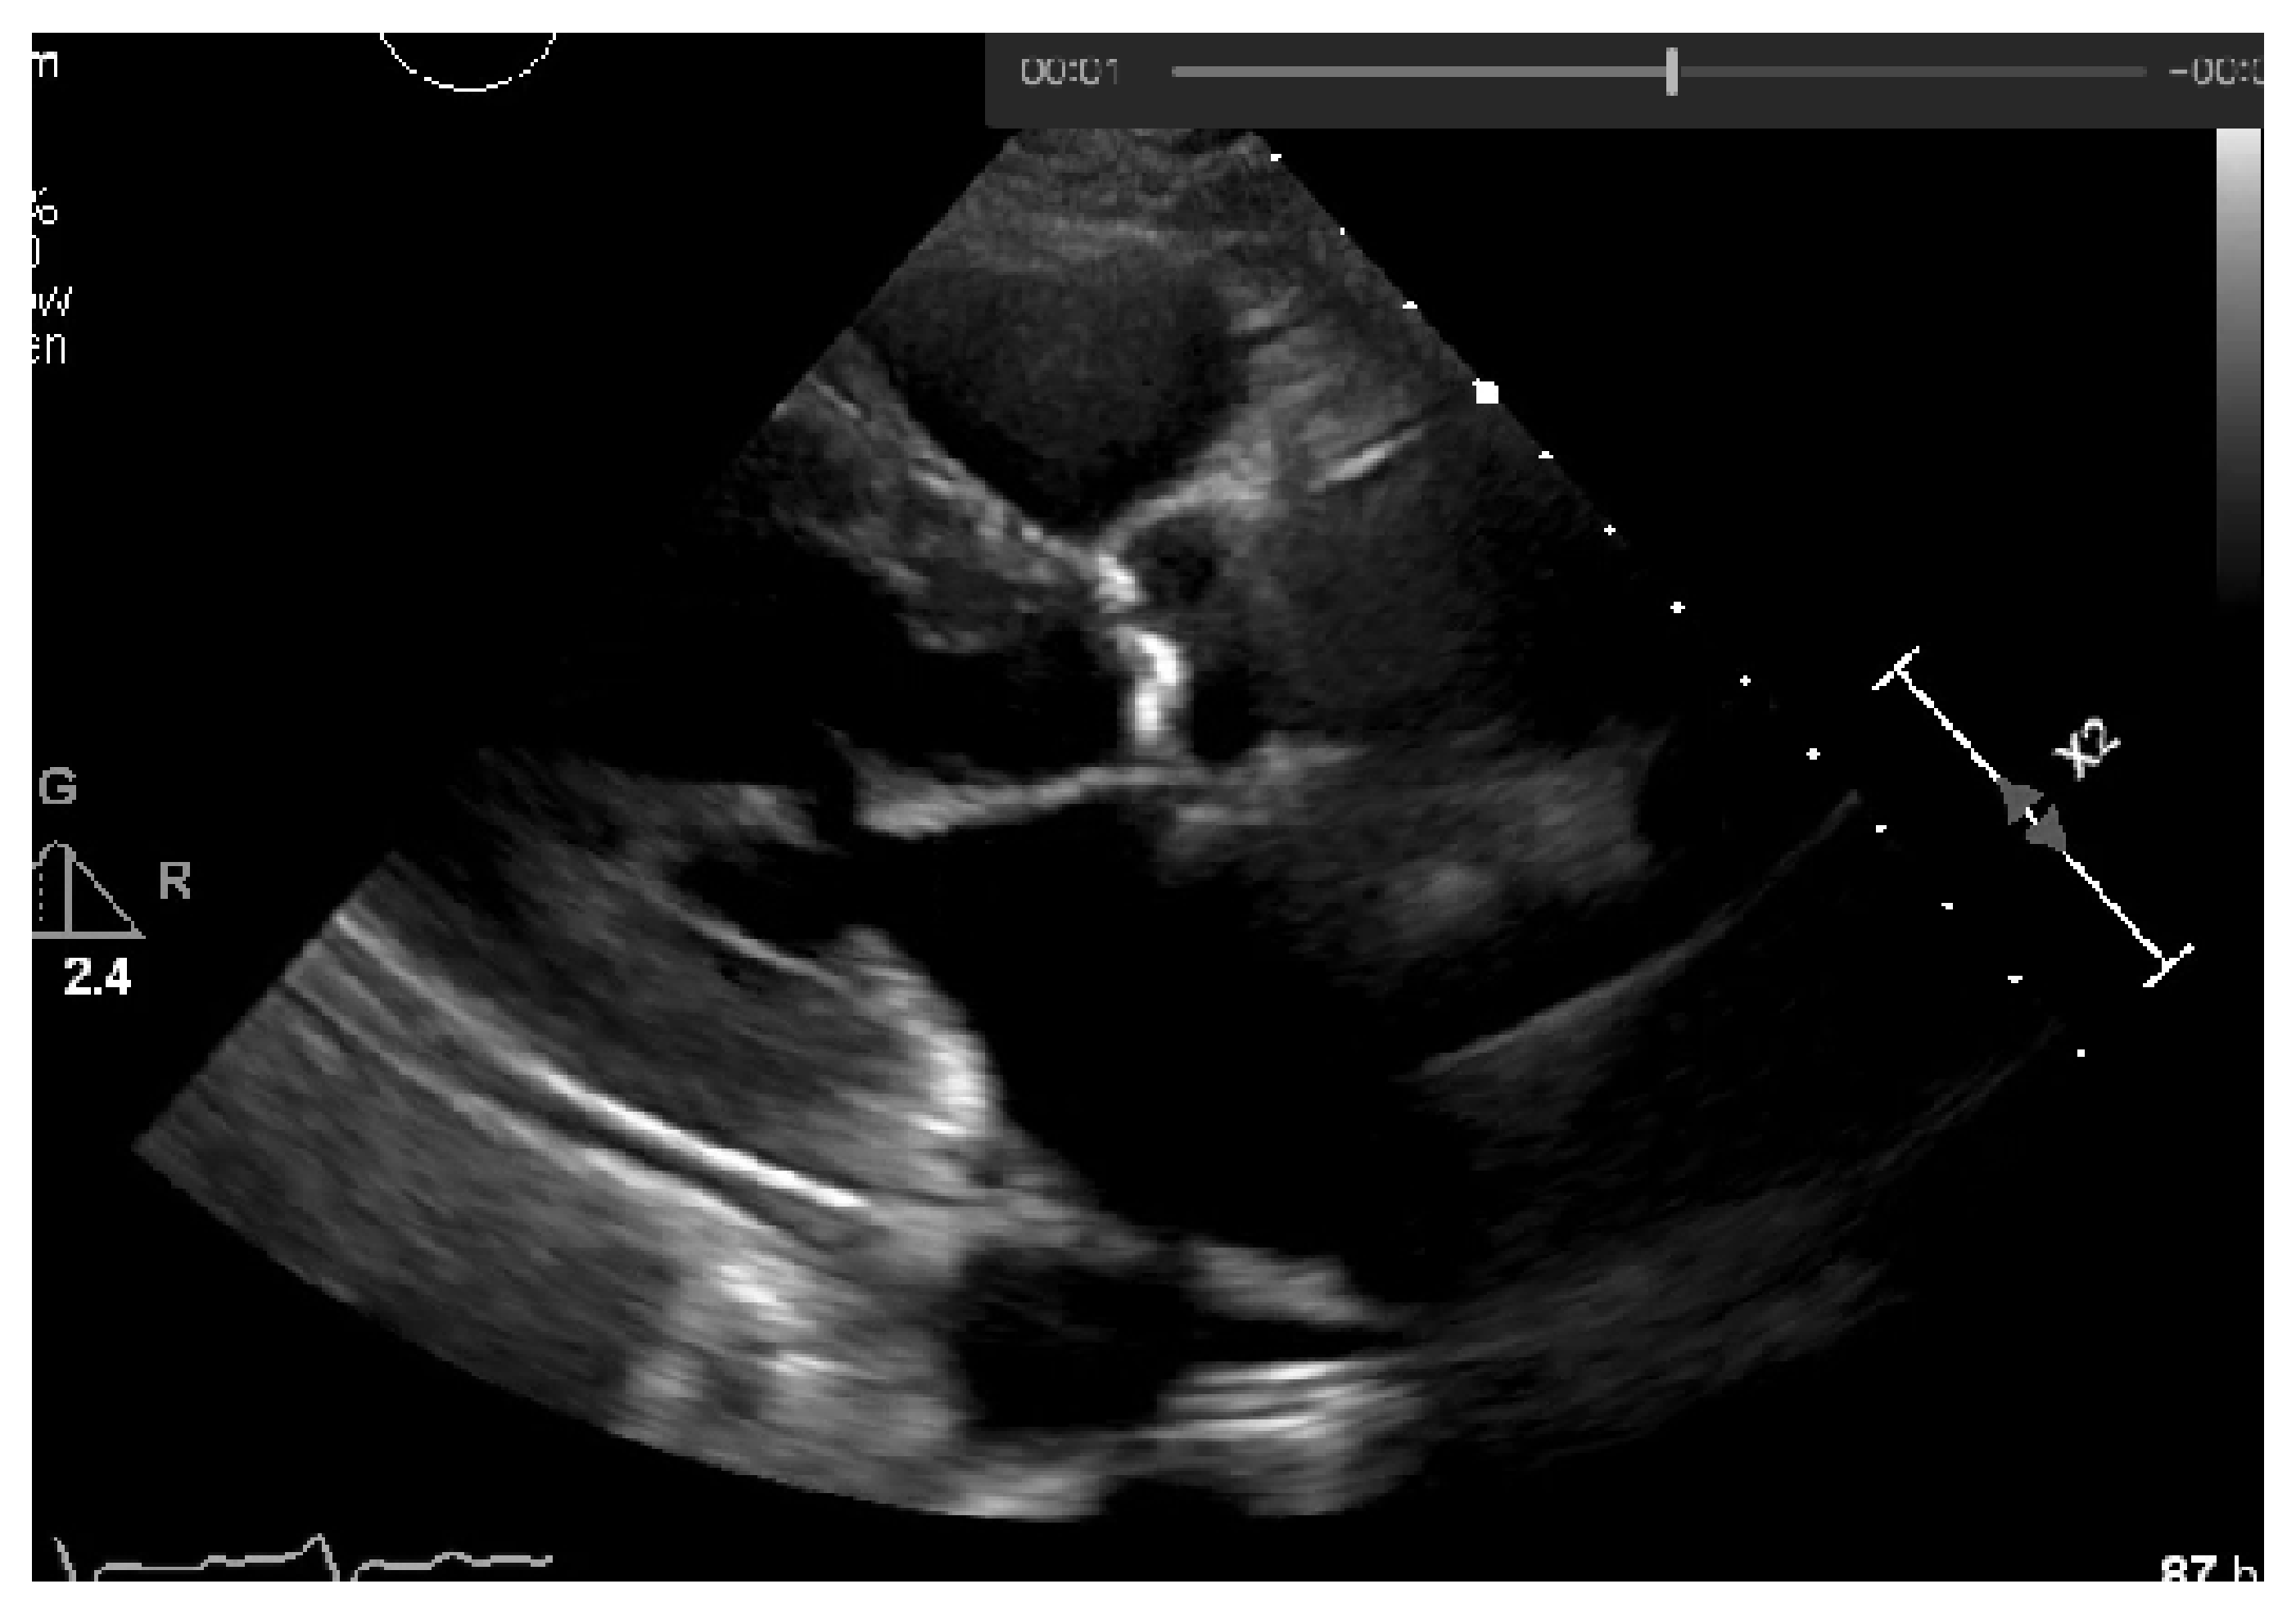

This initial constant threshold was weighted and defined by the experts in cardiology and echocardiography and the co-authors of this paper (AGA and LR), who have more than 20 years of experience. However, pixel intensities from echocardiographic images change with the acquisition parameter settings, such as image depth, ultrasound pulse frequency, and image compressing. Moreover, the post-processing level of gain intensity also changes the overall pixel intensity. Images collected with a combination of different parameter settings were analyzed, to test our normalization intensity values approach, and to identify an cut-offs for calcification in patients, with and without calcification, for controlling these parameters. Visual assessment by experts was used as our reference for calcium analysis. Since after collecting the echocardiography image there is a processing stage (gains are applied to the image), we would end up with an echocardiography image with different values of brightness and setting a constant binarization threshold would not provide good image segmentation. To tackle this issue, an adaptive normalization of our threshold was performed by adding the extra-brightness. This extra-brightness is taken from a region of the echocardiography that should be completely black, the left atrium cavity, as shown in Figure 17.

Achieving a dynamic threshold will normalize our echocardiography images, allowing our model to identify the calcium in different cases with different gains. The calcium presence can be seen in Figure 18 and is marked by a red circle.